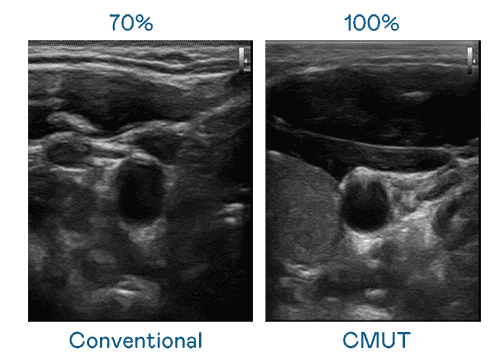

CMUT 技术是一种用电容式微机电元件来产生超音波讯号的技术。。。与传统 PZT 压电式技术相比,,,,CMUT 频宽增加 30%,,,,更宽频的超音波讯号让影像解析度大幅提升,,,是实现高影像品质医疗超音波扫描、、促进精准医疗发展的关键技术。。。

大频宽带来超清晰影像

超音波影像的解析度高低,,,,首先取决于探头能发出的讯号频宽。。。。尊龙集团 CMUT 可提供高清晰的超音波讯号,,,,提供高频宽、、、、高灵敏度、、、、影像纹理细节更高的超音波影像,,,协助医护人员缩短影像判读时间及利用精准的医疗影像进行诊断。。。。